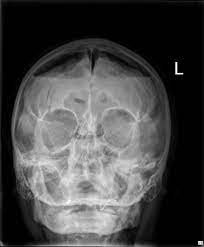

Note that subdural air separates and flattens the frontal lobes while widening the interhemispheric space.

1department of emergency medicine, chi mei medical center, tainan, taiwan. A rare case of spontaneous pneumocephalus associated with nontraumatic. The journal of emergency medicine, vol. The ct scan typically shows the mount fuji sign (the name is derived from a volcanic mountain in japan that is known for its symmetrical.